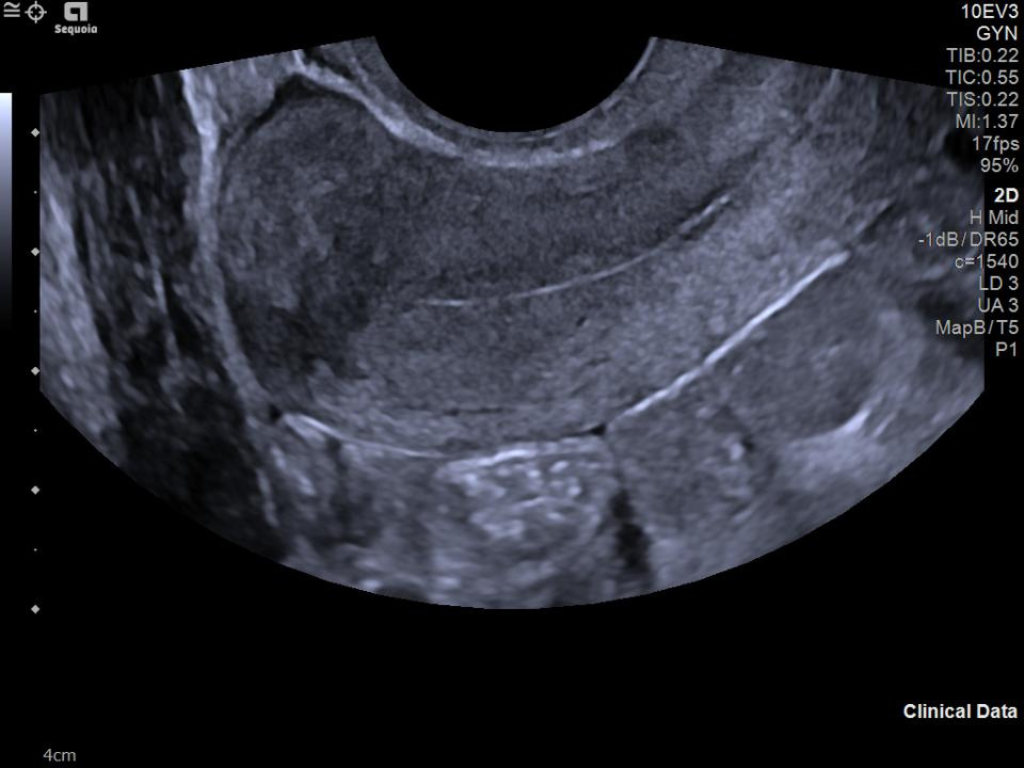

The ACUSON Sequoia is an advanced diagnostic tool that integrates cutting-edge technology and AI-powered applications to streamline diagnostic processes. This system is designed to cater to patient-specific needs, ensuring accuracy and efficiency in various clinical settings such as Radiology, OB/GYN, Shared Service and beyond.

The latest updates on ACUSON Sequoia use the power of groundbreaking AI for abdominal cases, includes advanced breast visualization to deliver new levels of image quality confidence, and tackles the toughest challenges in musculoskeletal imaging, all while saving your team from needless strain and pain.

A clearer, deeper perspective with optimal acoustics for each clinical use case. Expand your assessment with advanced tools that take ultrasound beyond its traditional role.